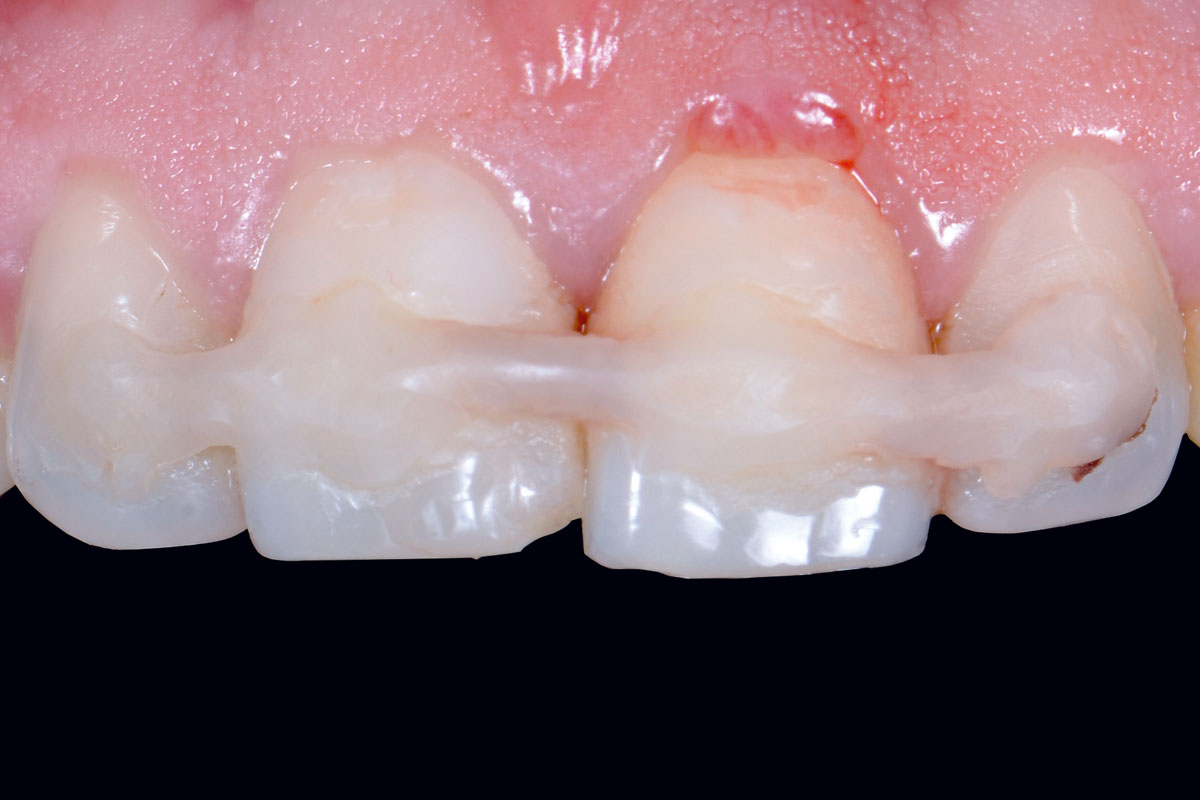

08/12 - Customized abutments in place

Treatment of a double root fracture in the aesthetic zone with cerabone® – Dr. J. M. Abarca